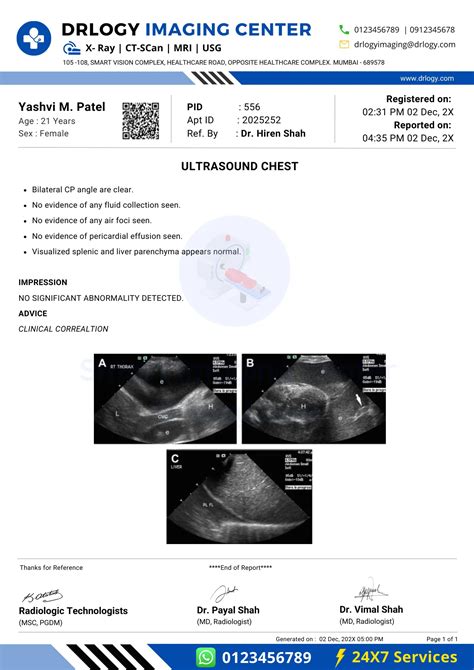

- Patient Information: This section includes the patient’s name, age, and relevant medical history. It is important to ensure the accuracy of this information for proper identification and reference.

- Indication for Examination: This describes the reason why the ultrasound was performed. It could be to assess a specific symptom, monitor a known condition, or evaluate a particular area of concern.

- Findings: The findings section is the core of the ultrasound report. It contains a detailed description of the structures visualized during the examination. The radiologist or sonographer will carefully evaluate each area of interest and note any abnormalities, measurements, or pertinent observations. It is vital to pay close attention to this section for accurate interpretation.

- Impression: The impression provides a concise summary of the findings and offers an interpretation of the ultrasound examination. This section often includes a diagnosis, assessment of the condition’s severity, and possible recommendations for further evaluation or treatment.

- Images: Ultrasound reports may include images that accompany the findings section. These images provide visual support and aid in understanding the written description. It is crucial to review the images carefully while referring to the corresponding findings.

- Conclusion: The conclusion section briefly summarizes the overall assessment and highlights any important clinical implications found in the report.